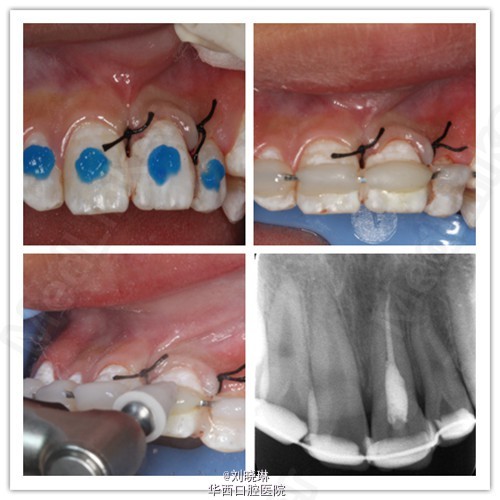

病人14岁,外伤导致上前牙脱落,患牙离体时间超过30小时。给患者讲明离体时间过长,患牙又未做正确方式保存,再植成功率低,患者要求试保留再植,术前签知情同意书。